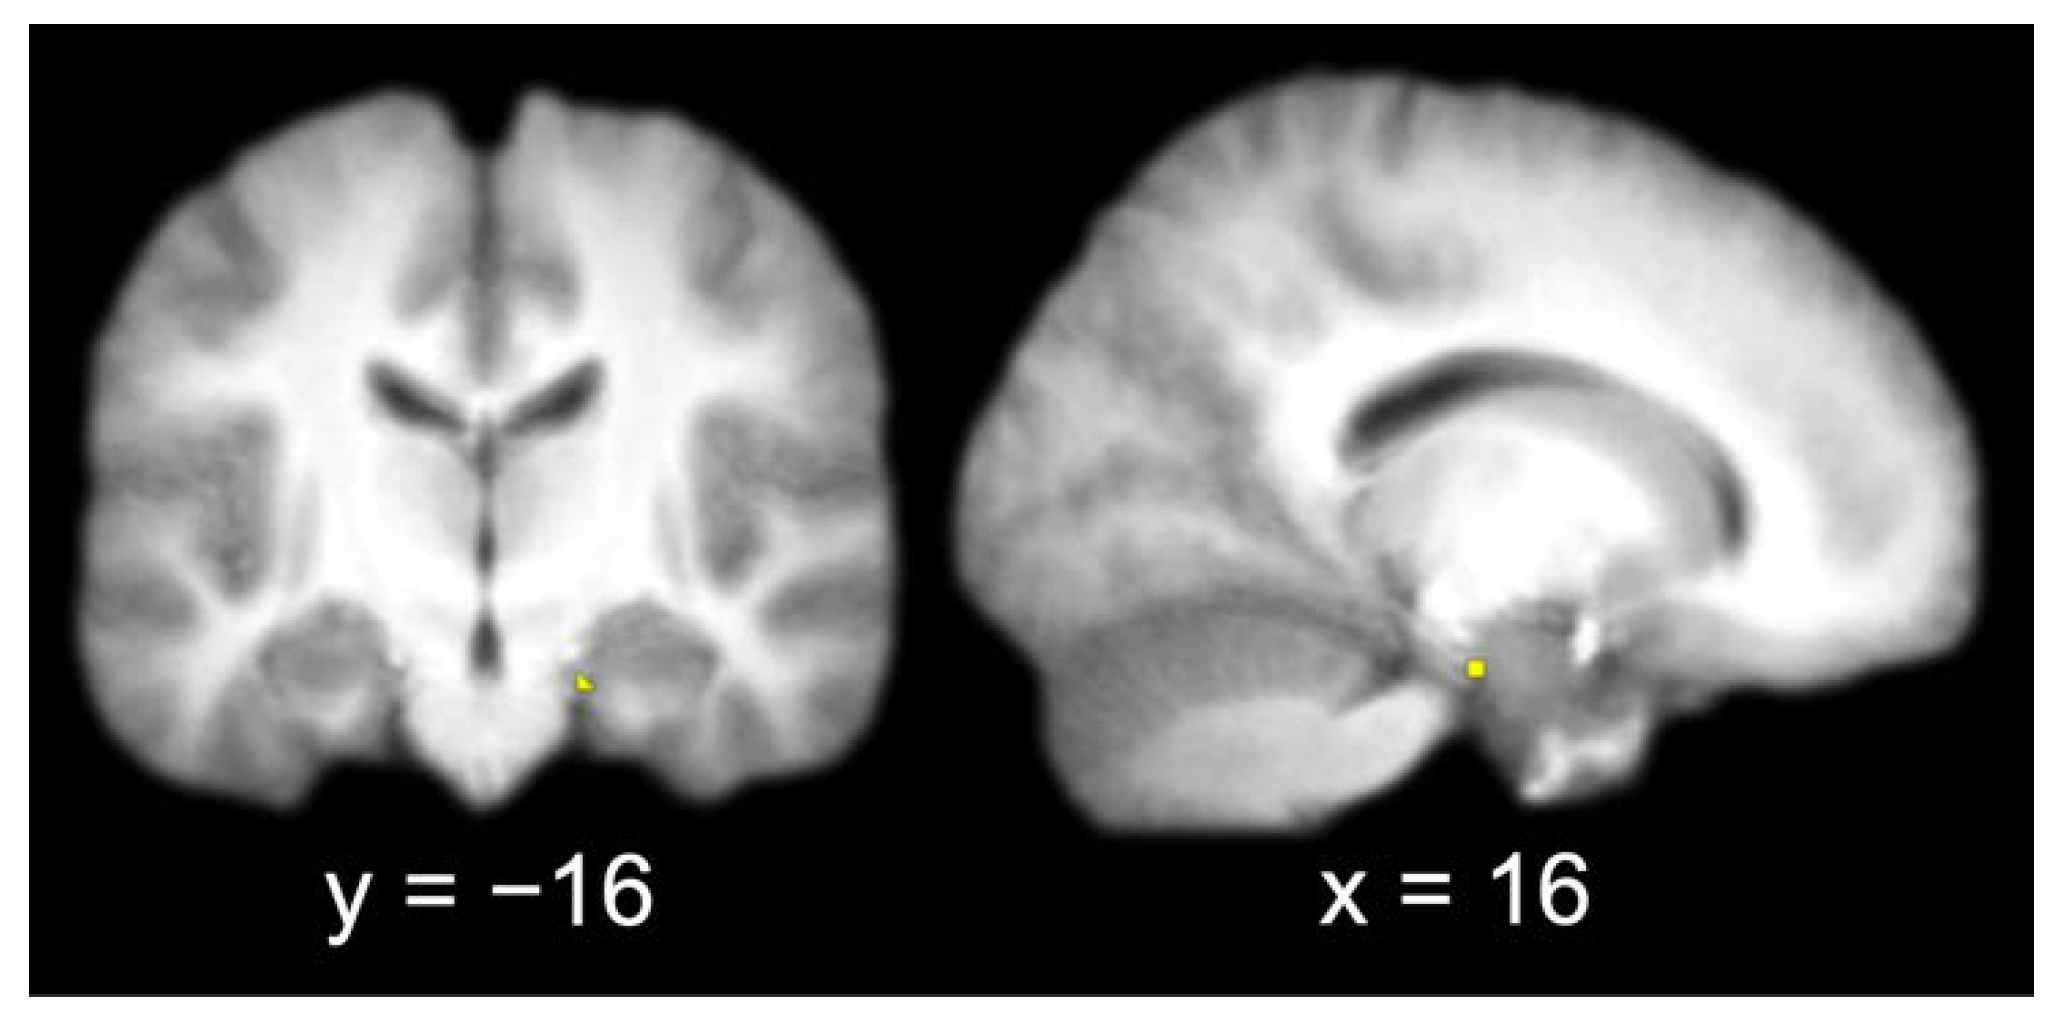

The group contrast of item hits versus misses produced a single activation in the right entorhinal cortex (x = 16, y = −16, z = −22). A 3 mm sphere centered at the most significant coordinate contained 6 voxels that were used as the seed for the functional connectivity analysis (Figure 3).

Figure 3.

Entorhinal cortex seed (identified by contrasting item memory hits and misses and extracting a 3 mm radius sphere around the most significant coordinate of the activation; left, coronal slice; right, sagittal slice).